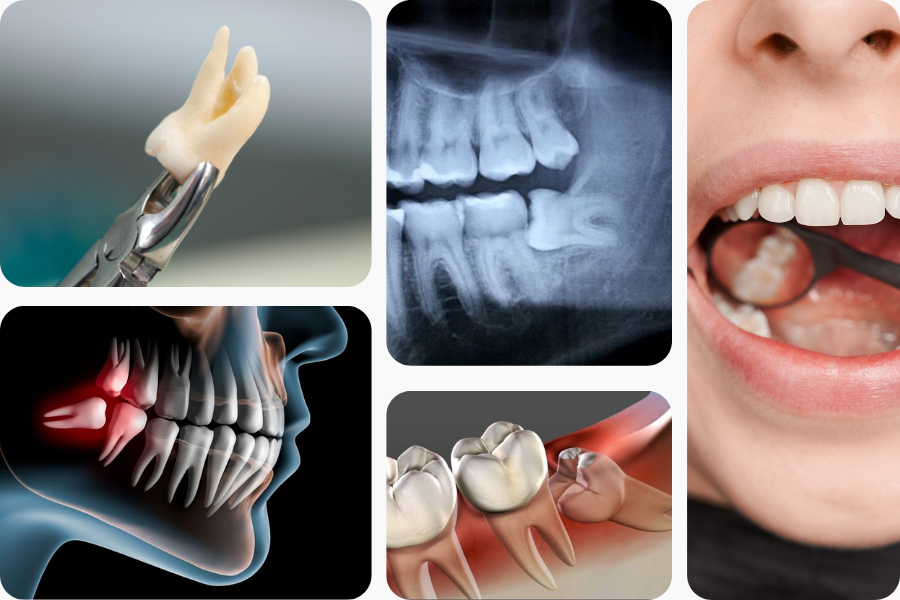

What is Wisdom Tooth Extraction?

Wisdom tooth extraction is a common oral surgical procedure performed to remove one or more wisdom teeth—the third set of molars located at the back of the mouth. These teeth often emerge in late adolescence or early adulthood and can cause problems if there is not enough space for them to grow properly. Issues such as impaction, crowding, infection, or decay frequently necessitate their removal.

The procedure typically involves numbing the area with local anesthesia, followed by careful extraction of the problematic tooth. In some cases, a small incision may be made in the gum to access the tooth. Wisdom tooth extraction helps prevent pain, infection, and future dental complications, supporting long-term oral health.